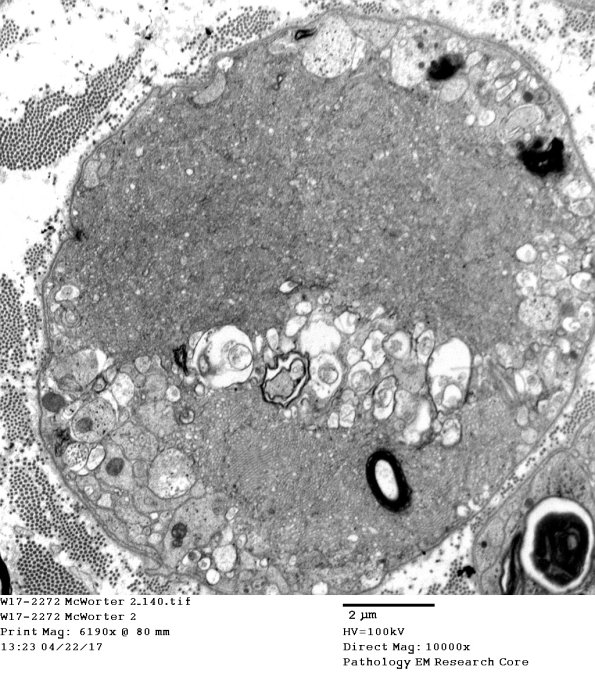

2C15,16 A mixture of vacuoles and vesicular myelin.